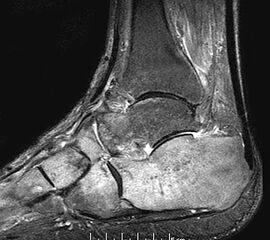

Diagnostische Methode der Wahl ist das MRT, das eine sichere Diagnosestellung erlaubt. Dabei kommt es  im betroffenen Knochen zur signalarmen Darstellung in der T1-Wichtung während T2 gewichtete Darstellungen als Folge des Ödems mit einer  Signalanreicherung in den betroffenen Skelettabschnitten und oft auch in den benachbarten Weichteilen imponieren

10.

Mitunter kommt es im Krankheitsverlauf zur verzögerten Migration des Ödems in benachbarte Skelettabschnitte (z.B. Migration vom Talus in die distale Tibia oder in den Kalkaneus) (Abb. 2 und 3), was den Krankheitsverlauf erheblich prolongieren kann.